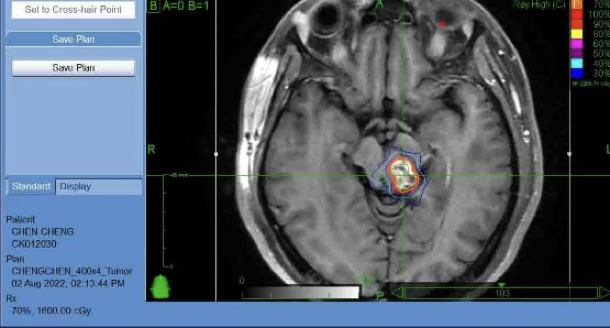

A female patient presented with a brainstem glioma, experiencing two months of weakness while walking and numbness in her right limbs. MRI revealed a tumor in the left brainstem, and pathology confirmed a brainstem glioma.

Dr. Wang Enmin developed a treatment plan combining CyberKnife with conventional radiotherapy for this challenging case. He explained: “We used five sessions of CyberKnife radiosurgery followed by 12–15 sessions of conventional radiotherapy. The goal was to escalate the dose inside the tumor using CyberKnife, while conventional radiotherapy covered potential tumor cells beyond the visible boundary.”

More than four years later, the patient remains in excellent condition, leading a normal life and working without restrictions. Dr. Wang emphasized the importance of regular MRI follow-ups. If small recurrences are detected, timely CyberKnife treatment can control progression. At her latest MRI check in August, the tumor had significantly shrunk.